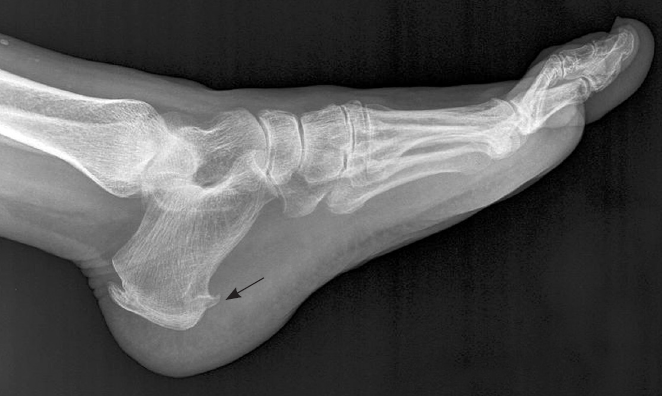

발바닥통증의 원인 고통성 족부 변형 (뼈 돌출 등)

- 발바닥의 뼈나 관절의 이상으로 인해 통증이 발생할 수 있습니다. 뼈의 돌출이나 과도한 뼈 성장(예: 발가락의 뼈가 튀어나오는 경우) 등이 그 예입니다. 이 경우 신발이 맞지 않거나 발에 가해지는 압력이 증가하여 통증이 유발됩니다.